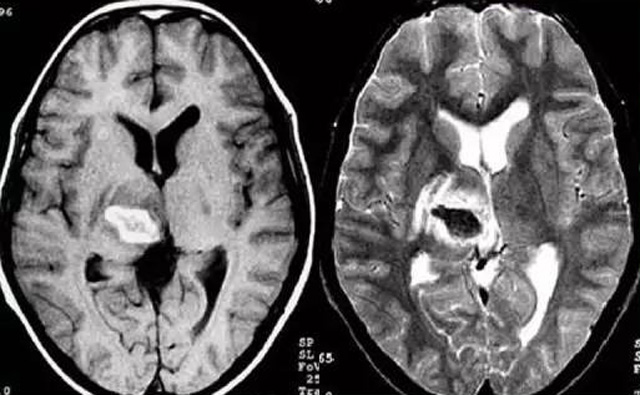

發(fā)現(xiàn)病人出血腦梗相關(guān)癥狀時(shí)候第一時(shí)間就醫(yī),需要攜帶以往的影像檢查資料。向醫(yī)生提供相關(guān)的病史基本資料。做影像檢查時(shí)候需要全身不攜帶金屬物品。檢查時(shí)候身體保持不動(dòng),不然偽影對(duì)檢查結(jié)果有干擾。磁共振MRI發(fā)現(xiàn)缺血性卒中后,幫助進(jìn)一步查找病因。由于CT上小腦跟腦干顱骨影響,容易導(dǎo)致漏診。MRI檢查可以對(duì)CT檢查不足的補(bǔ)充。短暫的腦缺血TIA也需要進(jìn)行影像檢查。短暫性缺血一般10幾分鐘后好轉(zhuǎn)。檢查目的可以確定TIA的病因。降低腦梗死的發(fā)生率。磁共振有助于排出TIA表現(xiàn)的顱內(nèi)病變,有診斷及時(shí)治療的價(jià)值。磁共振MRI檢查時(shí)間比較長(zhǎng),不太適合急診病人。但是可以發(fā)現(xiàn)腦干小腦的出血問(wèn)題。因?yàn)榧毙阅X梗死的早期和急性期,缺血區(qū)的腦組織還沒(méi)有完全壞死,頭顱CT不能顯示病灶,所以就需要MRI磁共振檢查,這個(gè)對(duì)陳舊跟亞急性出血顯示比較好。缺點(diǎn)性價(jià)比不高,費(fèi)用比較貴。頭顱的磁共振MRI在發(fā)病后的幾天CT的敏感降低時(shí)候發(fā)揮大作用。,MRI可作為診斷蛛網(wǎng)膜下腔出血和了解破裂動(dòng)脈瘤部位的一種重要方法,必要時(shí)進(jìn)一步進(jìn)行DSA檢查,幫助制訂臨床的手術(shù)治療方案,